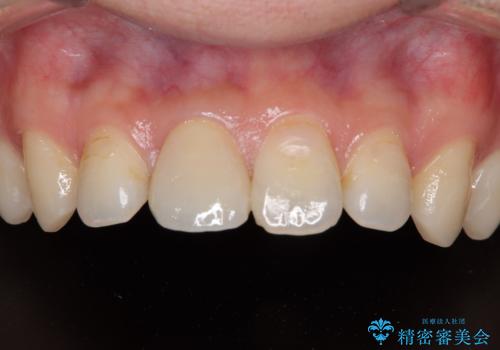

隣の歯と色が調和して、自然な仕上がりで満足されました。